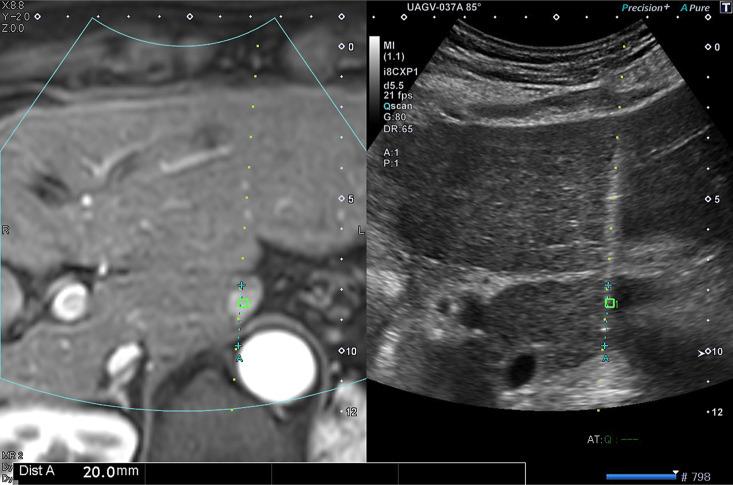

Globally, the incidence and associated mortality of primary liver cancer have been steadily increasing. Currently, 80% of cases are found in Asia. Curative resection is applicable in only 20% of patients; therefore, various nonsurgical treatment modalities have been developed. Image-guided percutaneous liver tumor ablation is regarded as the best option for treating early-stage hepatocellular carcinoma (HCC). However, skills and knowledge in ablation can vary among operators. Furthermore, Asia has the highest number of ablation procedures for HCC and the largest number of doctors performing ablation worldwide. Thus, the Asian Conference on Tumor Ablation has developed guidelines for HCC. These guidelines will discuss indications, pre-ablative diagnosis and planning, techniques, peri-ablative management, evaluation of therapeutic effectiveness, complications, post-ablative follow-up, prevention of recurrence, and treatment of recurrence for HCC.

在全球范围内,原发性肝癌的发病率和相关死亡率一直在稳步上升。目前,80%的病例在亚洲被发现。根治性切除术仅适用于20%的患者;因此,已开发出各种非手术治疗方式。影像引导下经皮肝肿瘤消融被认为是治疗早期肝细胞癌(HCC)的最佳选择。然而,消融的技术和知识在操作者之间可能存在差异。此外,亚洲进行HCC消融手术的数量最多,全球进行消融手术的医生数量也最多。因此,亚洲肿瘤消融会议制定了HCC指南。这些指南将讨论HCC的适应证、消融前诊断和规划、技术、消融期管理、治疗效果评估、并发症、消融后随访、复发预防以及复发治疗。